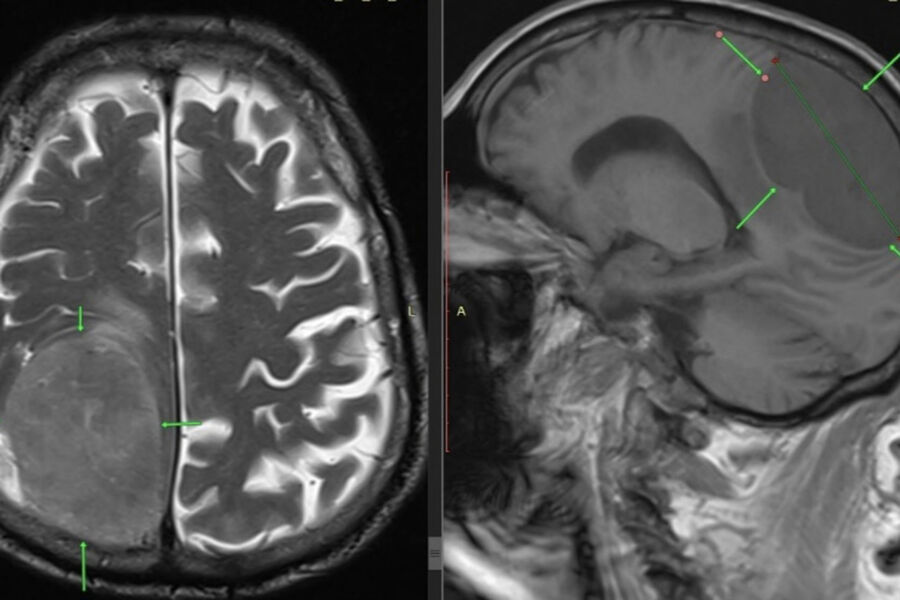

Российские врачи спасли пенсионера с опухолью мозга размером с лимон

В Пятигорске медики спасли 85-летнего мужчину, у которого в голове была опухоль размером с лимон. Об этом сообщает пресс-служба ГКБ Пятигорска.

Пожилого пациента доставили в больницу с симптомами, напоминавшими инсульт — у него отказала левая нога и парализовало левую половину тела. Врачи выявили причину недомогания мужчины. Оказалось, что у него в голове находится новообразование размером восемь на семь сантиметров.

Нейрохирурги провели пенсионеру костно-пластическую трепанацию черепа и полностью удалили опухоль. После вмешательства состояние мужчины быстро улучшилось, у него восстановилась двигательная активность. Гистология подтвердила доброкачественный характер удаленной опухоли.